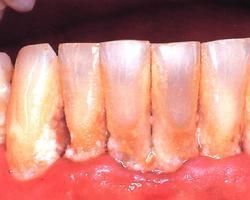

牙齦病慢性單純性齦炎是自覺症狀不明顯,但常不刷牙、咀嚼、吮吸等引起牙齦出血的現象。牙齦緣和齦乳頭充血、水血、水腫,由原來的粉紅色變為深紅乃至紫紅色。齦溝內滲出物增多,輕探之,即易出血;妊娠期齦炎是緣齦和齦乳頭明顯發紅、腫大、鬆軟、發亮,觸之易出血。有時個別齦乳頭可快速生長如球狀,觸之柔軟,並可有蒂,稱妊娠瘤;牙齦增生所包括的藥物性牙齦纖維增生是指增生起於牙列中唇頰或舌、齶側的緣齦或齦乳頭,開始呈小球狀突起,隨著增生的繼續進展,齦乳頭可互相靠近,最終連線在一起而復蓋大部牙面.一般不出血,無痛。牙齦纖維瘤病表現為口內大部以至全部牙齦呈瀰漫性增生,直達膜齦聯合處,增生牙齦顏色正常,觸之堅實,表面光滑或呈結節狀,點彩明顯,不易出血。